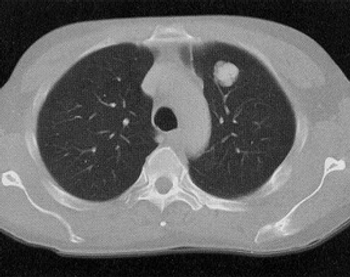

During routine chest imaging a 35-year-old woman is found to have a coin lesion in the right upper lobe. What is your diagnosis?